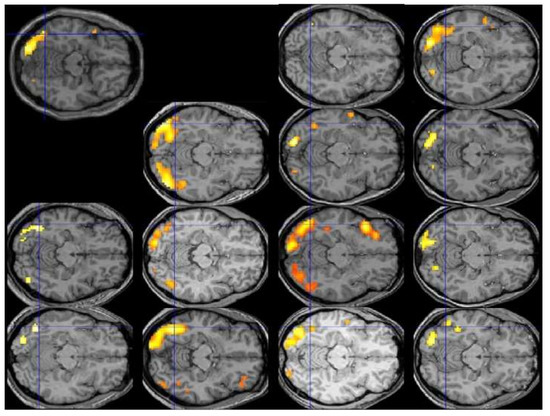

Lest the reader be inclined to dismiss this admonition as implausible or overly pedantic, Figure 1 displays the individual patterns of activation for the contrast of reading vs. fixation in the first 13 participants of Protopapas and colleagues [63], all analyzed and displayed using exactly the same procedure and criteria, along with their group average (top left). The crosshair centers on the group local maximum, within the visual word form area, which is the most robustly activated area in this sort of contrast across studies and languages. We would be hard-pressed to say what the typical pattern is by looking at the individual images, despite the robustness of the group finding. In fact, we might be tempted to consider some of these participants to be atypical, especially with respect to the group result, even though none of them had any reading difficulties.

Analysis of activation patterns at the level of individual brains, performed over large representative samples, is the only way to find out what is typical, if typical patterns do in fact emerge, and how large deviations from them are uncommon enough (by some arbitrary criteria) to be considered truly atypical, before the typical and atypical patterns can be related to behavioral manifestations such as good vs. poor reading. Unfortunately, the current state of the art in functional neuroimaging does not permit any judgments regarding typicality of activation, much less proclamation of any patterns (or individual brains) as “atypical”. It should then be clear by now that the existing fMRI findings, suggesting that the areas most consistently activated among a group of good readers are not entirely identical with the areas most consistently activated among a group of poor readers, do not imply that any of the good or any of the poor readers do in fact exhibit overall similar or different patterns of activation, typical or atypical.